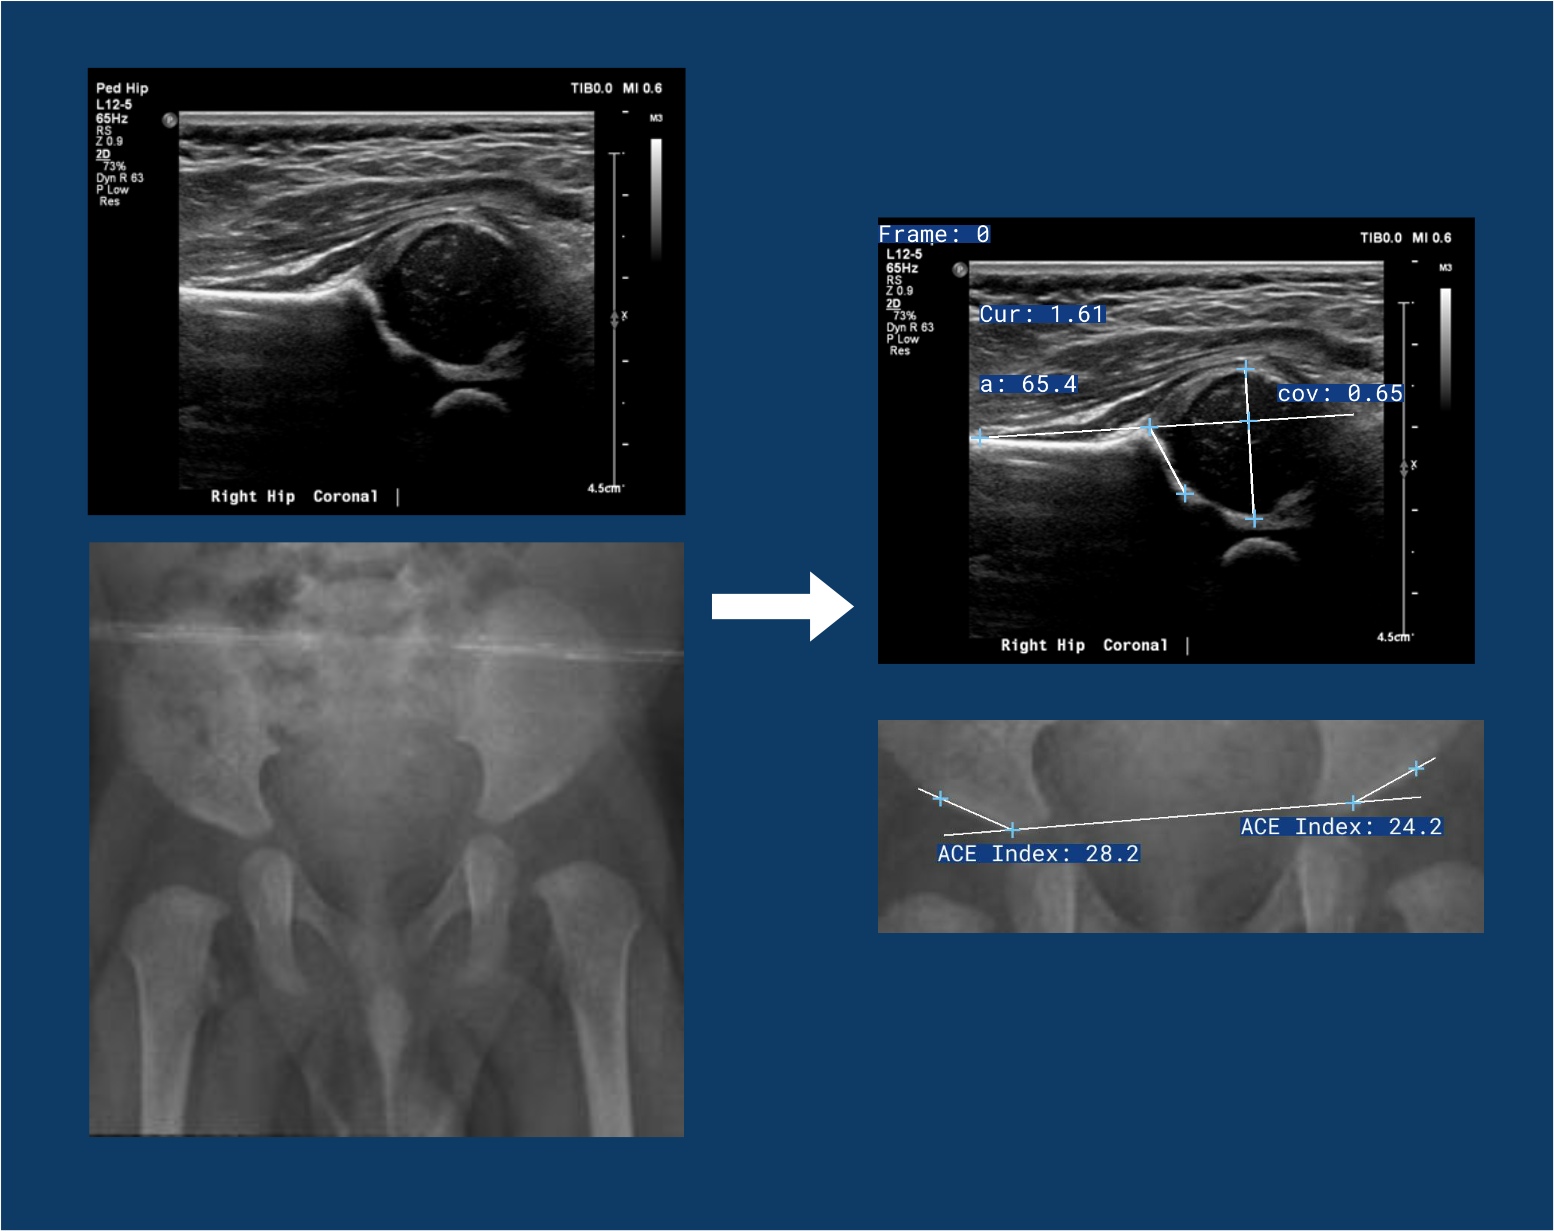

Retuve (from the scottish gaelic Ri taobh meaning beside) is a framework for analysing infant hips. It is designed to be a flexible and extensible framework that can be used by developers, AI researchers and clinicians.

It takes in raw hip Ultrasound and X-Ray images, and outputs a report with the labelled images, and the results, exactly as a clinician would.

Attribution of the above Ultrasound Images: Case courtesy of Ryan Thibodeau from https://radiopaedia.org 172535 (https://radiopaedia.org/cases/172535)

Attribution of the above X-Ray Images: Fraiwan, Mohammad; Al-Kofahi, Noran; Hanatleh, Omar; ibnian, ali (2022), “A dataset of DDH x-ray images”, Mendeley Data, V2, doi: 10.17632/jf3pv98m9g.2